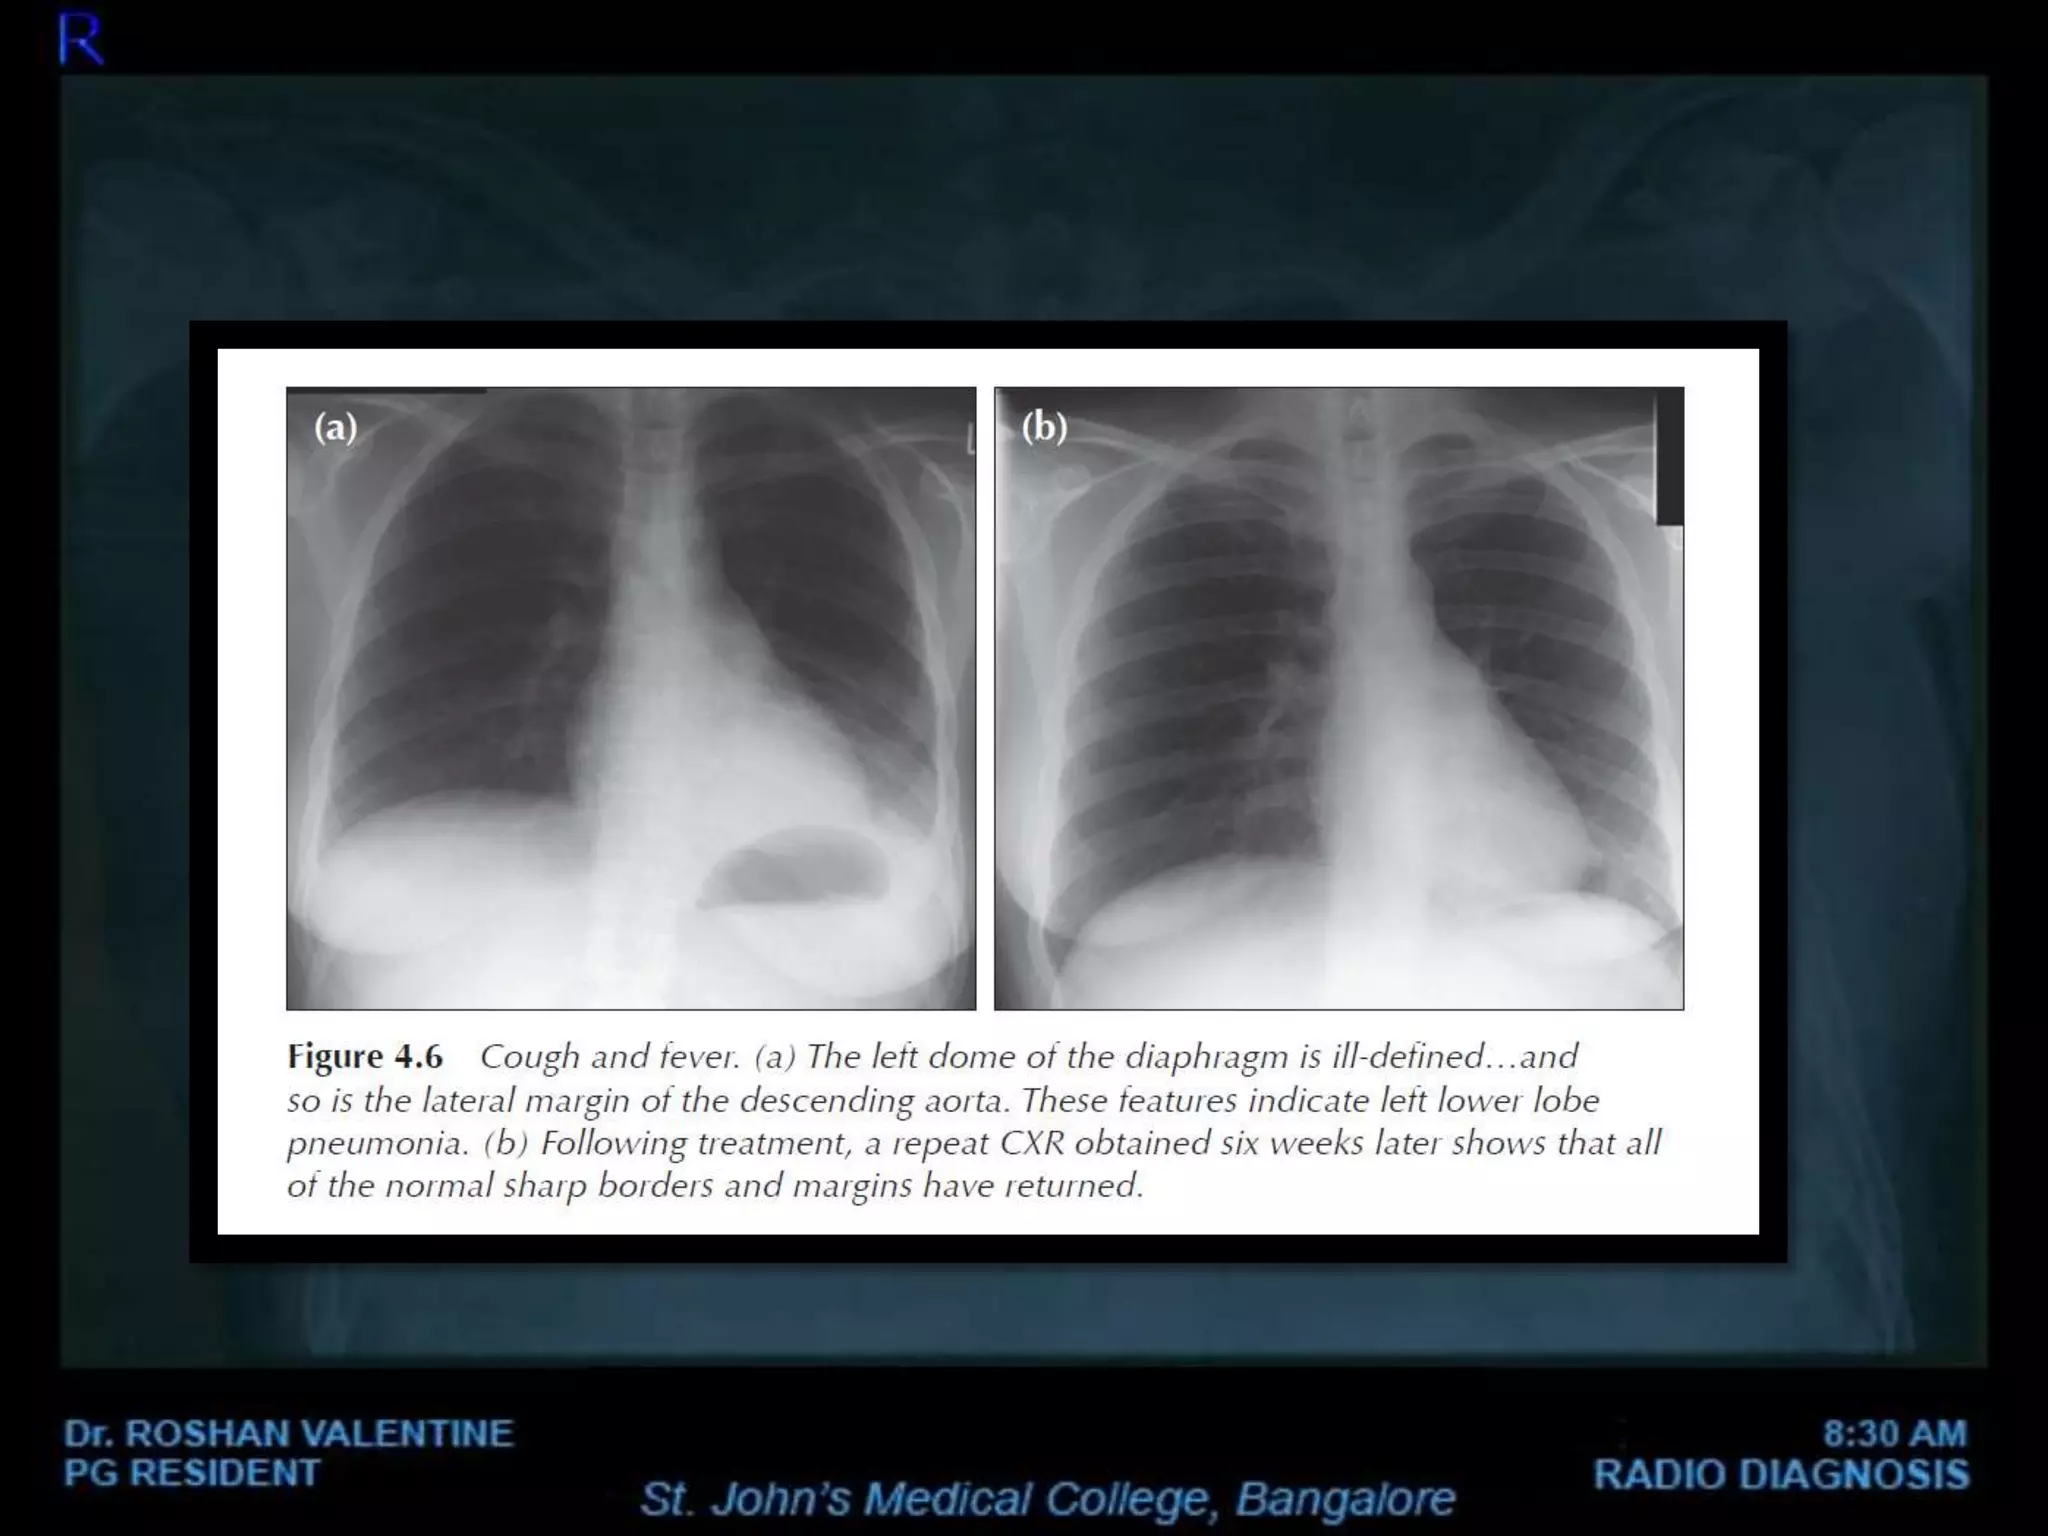

• Pneumonia: Inflammation of the lungs, often caused by bacterial, viral, or fungal infections.

Consolidation refers to the replacement of air in the lungs with fluid, cells, or other material. It appears as an area of increased opacity on the X-ray. Common causes include pneumonia and pulmonary edema.

A 65-year-old patient presents with fever, cough, and shortness of breath. The chest X-ray shows consolidation in the right lower lobe. The patient’s history of recent travel and exposure to sick contacts suggests a bacterial infection. Further investigations, including blood cultures and sputum analysis, confirm the diagnosis of pneumonia.